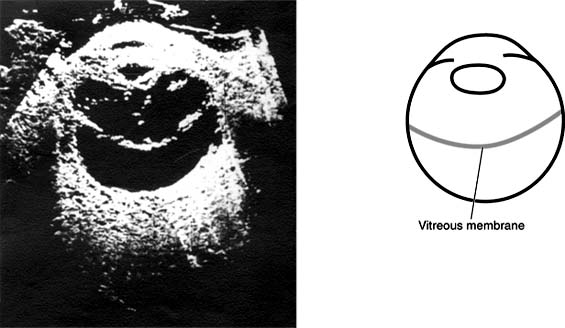

B-scan ultrasonography is an important diagnostic tool used in many posterior segment problems associated with gross vitreous opacification (Figure 9-2). Where light-dependent ophthalmoscopes and slitlamps provide insufficient information, skillful use of B-scan ultrasonography can provide much information about the vitreous and adjacent structures. For example, it is possible to identify and locate vitreous membranes (Figure 9-3), vitreoretinal relationships and retinal detachments greater than 1 mm in depth (Figures 9-3, 9-4 and 9-5), scleral ruptures, and intraocular foreign bodies (even nonlucent plastic and glass).

Figure 9-4

Figure 9-4: Vitreous membrane extending along posterior limiting membrane of vitreous from ora to ora. Retina is in place. (Reproduced, with permission, from Coleman DJ: Ultrasound in vitreous surgery. Trans Am Acad Ophthalmol Otolaryngol 1972;76:469.)